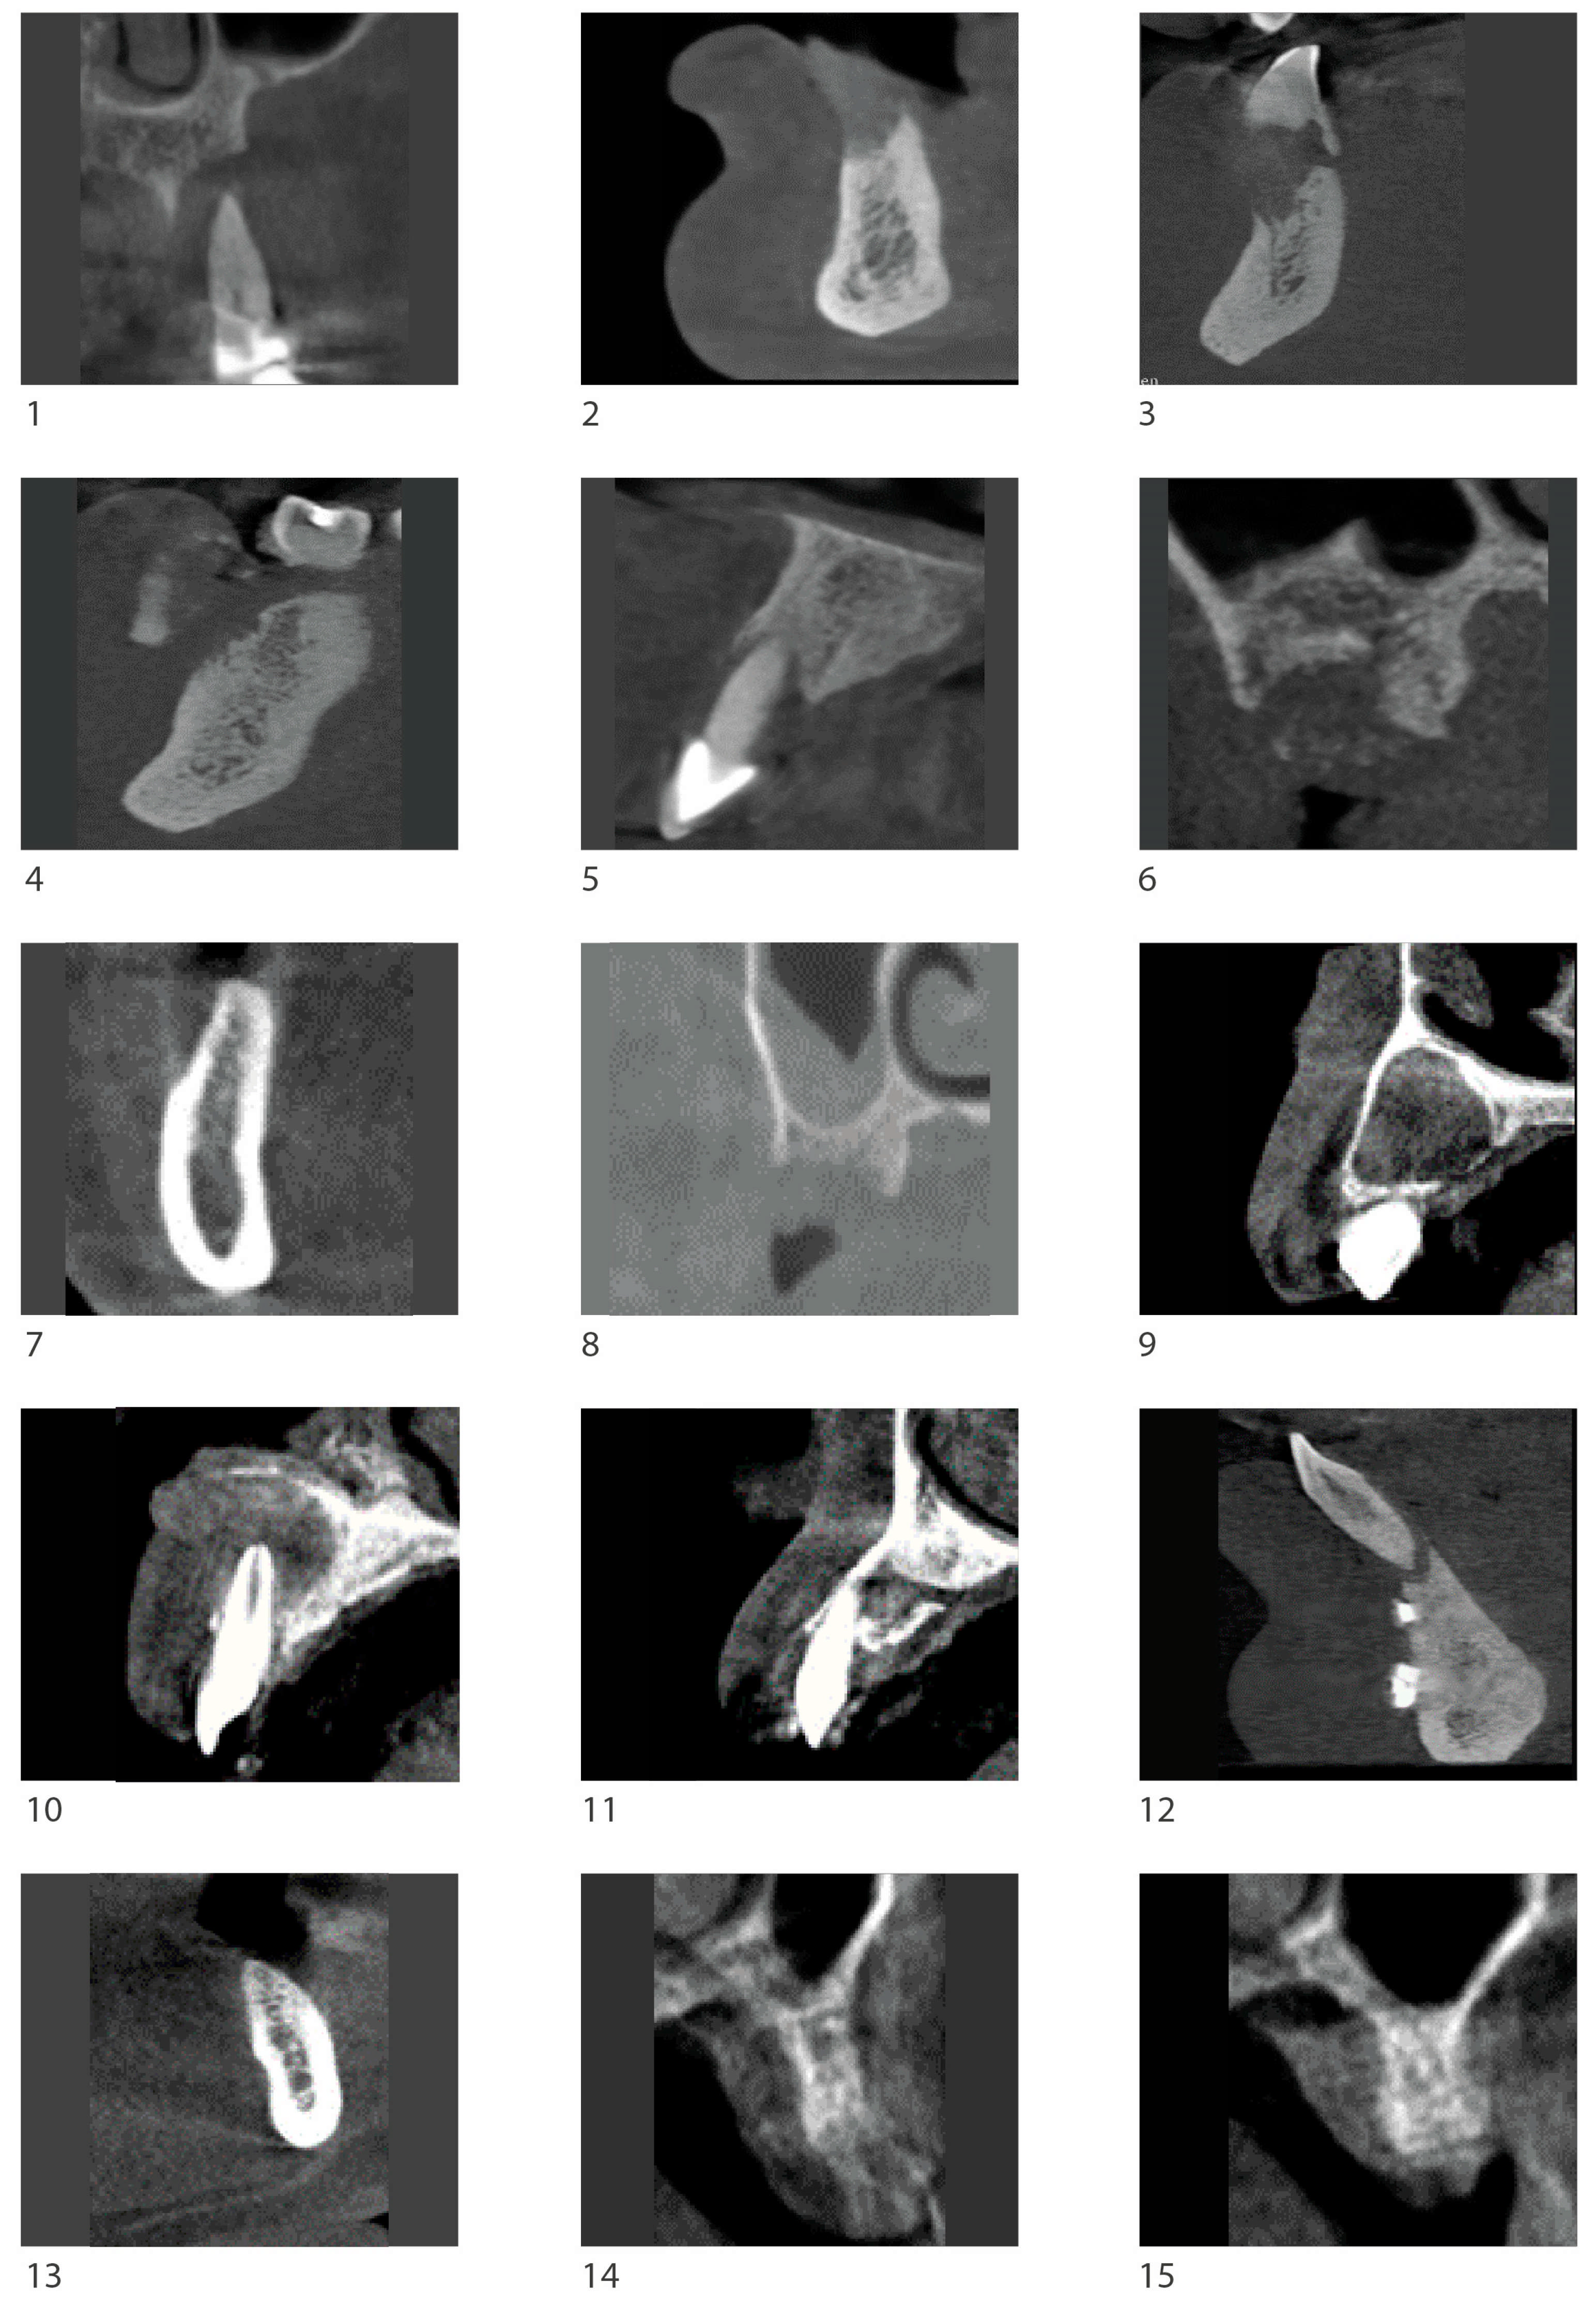

3.1. Radiological Observation